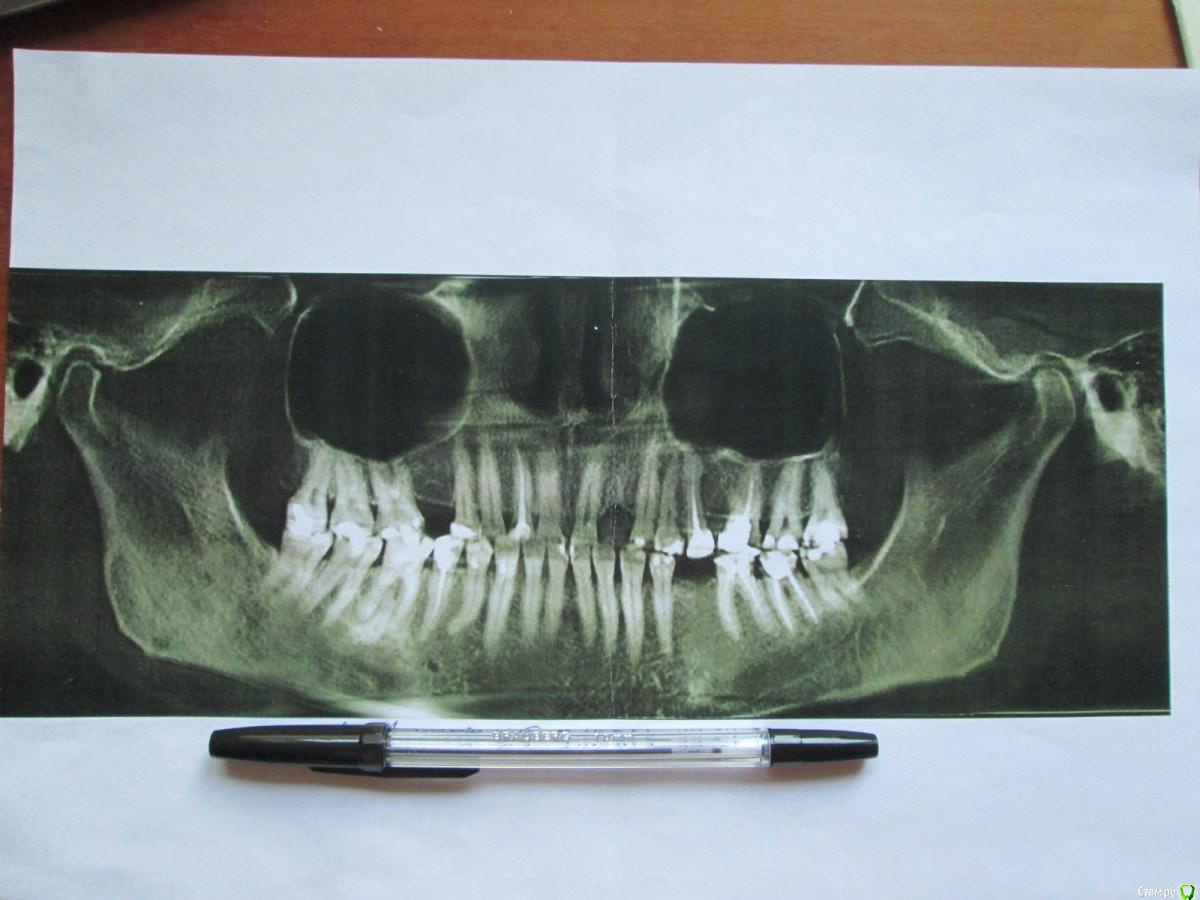

LOLga777 Опубликовано 24 ноября, 2019 Поделиться Опубликовано 24 ноября, 2019 (изменено) Здравствуйте, уважаемые врачи.37-й зуб. Депульпирован, стояла большая пломба. В 2013 году откололась наружная стенка зуба, скол близко к корню. Стоматологом № 1 был поставлен штифт, коронка восстановлена пломбой (фото с торчащим штифтом от 2013 года). Через год наружная часть пломбы откололась прямо по штифту, так ходила три года, ничего не царапало, не мешало. В 2016 году стоматолог № 2 в поликлинике уговорила запломбировать, в результате сделала скошенную наружную часть пломбы. Фото ротовой полости справа от 07.2019 г. прилагаю. Вопрос: что делать с 37-й зубом? Хирург не хочет удалять, говорит, что можно восстановить пломбой, и боится повредить 36-й. Не знаю, видно ли на снимках, в каком канале стоит штифт и можно ли поставить еще один штифт (второй штифт врач не поставила, насколько я помню, из-за того, что будет дороже и еще что-то там может не выдержать). Без второго штифта пломба, повторяющая анатомическую форму зуба, я считаю, простоит максимум год. С 36-м зубом тоже непонятно что делать, не идет ли там процесс кариеса на корне… Между корнями что-то черное (на КТ и 2016 года и 05.2019 года). Не хотелось бы покрывать коронкой зуб с гранулемой между корнями. Стоматолог предложил рассверлить пломбу и посмотреть.У меня ВОПРОС: можно ли будет что-то увидеть после рассверливания зуба, если процесс идет под «дном»? После сверления снимется еще часть тканей, а их там и так мало. По вкладкам и коронкам на 37-й зуб, наверное, надо продублировать тему в раздел «Протезирование». P.s. Есть большое количество других проблем Изменено 24 ноября, 2019 пользователем LOLga777 Ссылка на комментарий